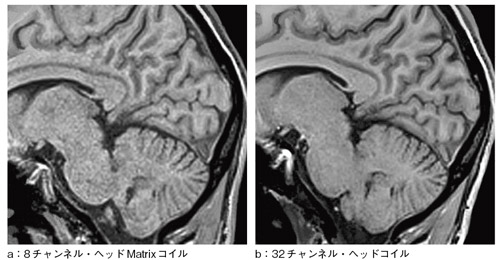

米国・ボストンのMassachusetts General Hospital(MGH)とシーメンスの共同開発により,32チャンネル・ヘッドコイルの開発が進んでいた(図1)。ヘルメットのような素体に32個のコイルを配置したヘッドコイルは,各コイルから配線が飛び出すという異様な形状をしていた。開発は,3T装置用に進められ,標準コイルとの信号ノイズ比などが検討されてきた(図2)。このコイルは後に,1.5T,3T用の32チャンネル・ヘッドコイルとして製品化されている(図3)。

図2 8チャンネル・ヘッドMatrixコイルと32チャンネル・ヘッドコイルとの比較

MAGNETOM Trio, A Tim System, 3D FLASH, 1mm isotropic, PAT 12, TA=1min20s